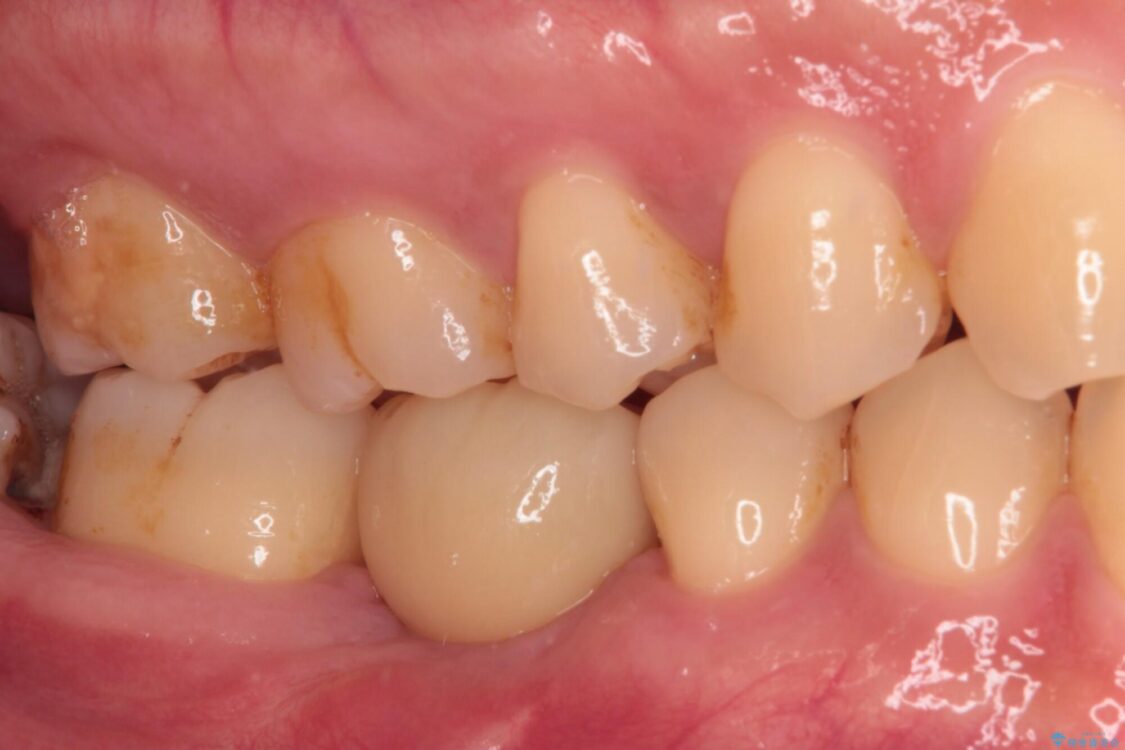

• 空いている時間を利用して通院 奥歯のインプラント治療 治療後画像